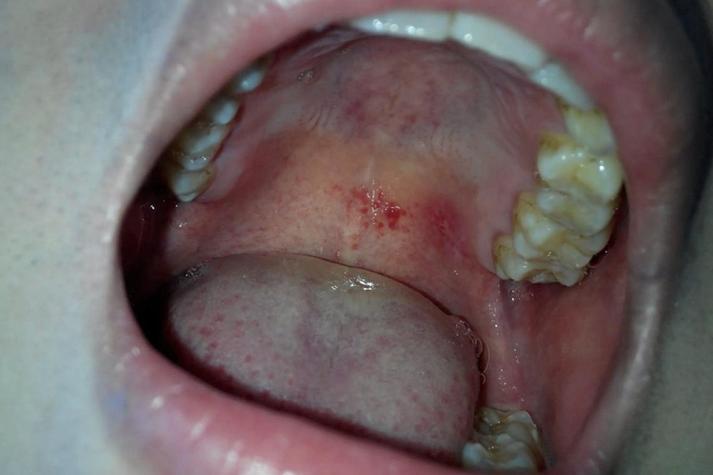

口腔上颚红斑上火照片 🔍 口腔上颚红斑的常见类型及外观描述 最常见:创伤性红斑/溃疡(符合“上火”或“咬伤”描述) 外观描述: 通常发生在上颚硬区(较硬的骨头部分),靠近牙齿或小丘状结构(切牙乳头)附近。 表面是一个边界清晰、圆形或椭圆形的红色凹陷区域(溃疡)。 溃疡中心可能覆盖一层淡黄色或灰白色的假膜(纤维蛋白渗出物)...